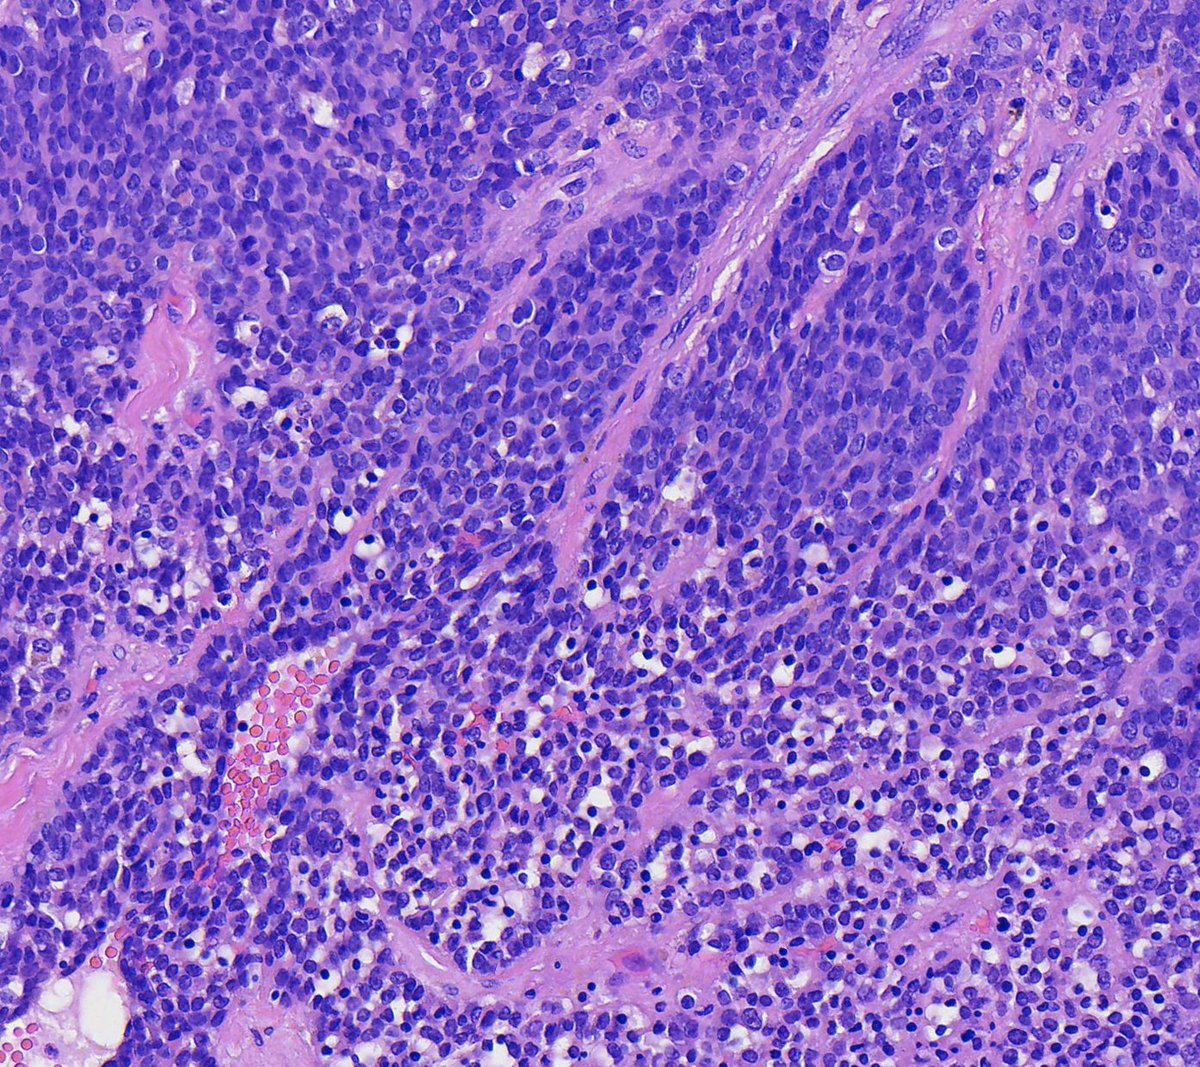

Couldn't be more excited to announce the launch of pathlibrary.com, the virtual slide site I wish had existed during my pathology residency. You can:

- See annotated histologic features